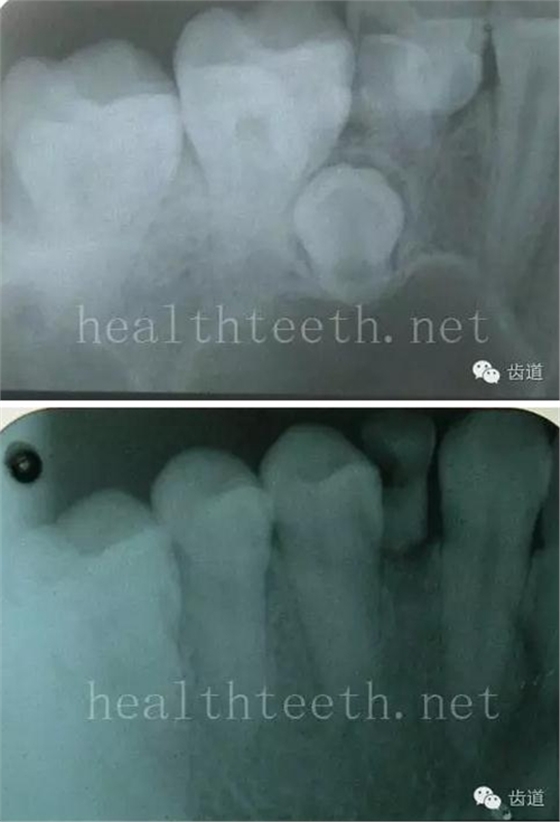

牙片顯示牙槽骨的垂直吸收

外院做的牙周固定,牙片顯示牙槽骨的水平吸收